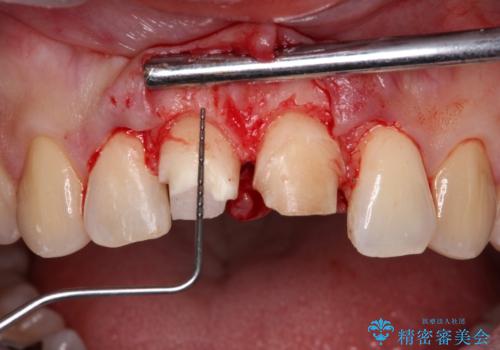

失活した歯は、根管治療を行った後に部分矯正により歯根を引っ張り出し、歯周外科処置により左右の歯肉の位置が揃えることとしました。

強い衝撃を受けた歯であるため、定期的にレントゲン撮影を行い、歯根吸収が起きていたり、神経が失活していたりしないか確認を行い、ある程度安定したところでオールセラミッククラウンにて補綴治療を行うこととしました。